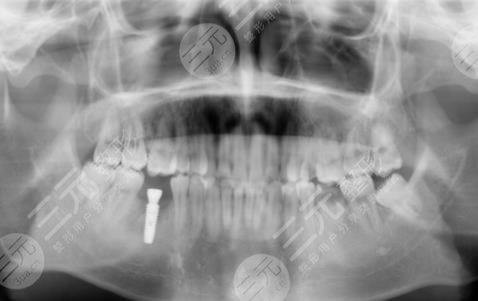

因?yàn)槲艺娴氖窒矚g吃糖,也就是很喜歡甜食,幾乎每天都有很多的糖攝入,有的時(shí)候連吃米飯我想要吃甜的,這就導(dǎo)致了我的年紀(jì)輕輕牙齒就蛀了,因?yàn)樘浅远嗔?,剛開始的時(shí)候還只是進(jìn)行補(bǔ)牙,但是隨著時(shí)間越來(lái)越久,我的牙齒的孔洞越來(lái)越大,然后沒(méi)有辦法就是拔掉了,我想著一直去補(bǔ)也不是問(wèn)題,就跟父母商量之后,來(lái)到了鎮(zhèn)江口腔醫(yī)院進(jìn)行種植牙。

醫(yī)生看了我的牙齒情況之后,為我判斷了幾顆比較需要進(jìn)行種植牙的地方進(jìn)行了拔除。大概在拔完牙,一星期后我進(jìn)行了種植牙,剛種上的時(shí)候還是覺(jué)得挺不舒服的,但是隨著時(shí)間的推移,我逐漸適應(yīng)了自己的種植牙,并且種植的牙齒比之前更加潔白,它不單單解決了我的口腔問(wèn)題,還讓我整個(gè)人的氣質(zhì)都上升了不少呢。